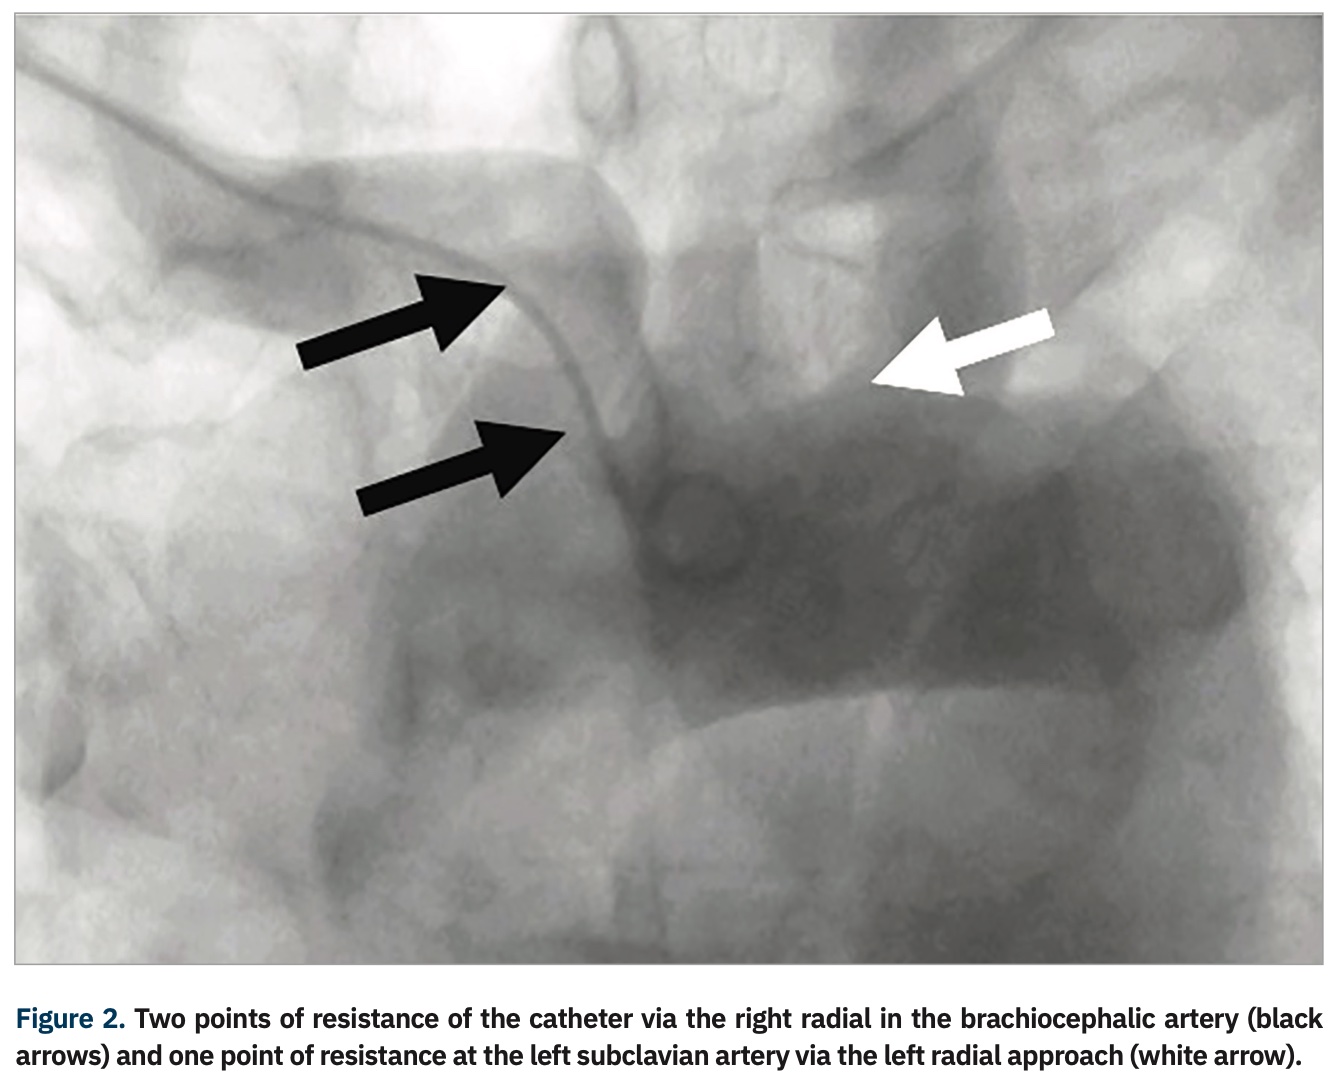

A review of 2100 failed transradial approaches for PCI found age >75 years (P<.001); prior coronary bypass surgery (CABG) (P<.001), and height <5 feet, 5 inches (165 cm) (P=.02) as independent predictors.9 Another study examined 1609 patients and found previous CABG, cardiogenic shock, and female sex as multivariable predictors for transradial failure of PCI (with right radial the default for transradial procedures, except in the case of prior CABG).10 Although a more experienced radial operator will often overcome the challenges of a right radial approach, there are still some patients where the majority of operators favor femoral access, such as patients with history of CABG. In a subgroup of patients (Table 1), access via the left radial artery may allow programs to “stay radial”. The catheter passing via the left arm follows a similar path as the femoral approach, with only one area of resistance in its path, at the left subclavian-aorta junction; conversely, the catheter passing via the right arm has two areas of resistance in its path, at the subclavian-brachiocephalic and the brachiocephalic–aortic junctions (Figure 2).11 An example of the analogy is the ease of right radial in those with situs inversus totalis (Figure 3), where with only one spot of resistance, the typical femoral catheters can be used easily via the right wrist.12